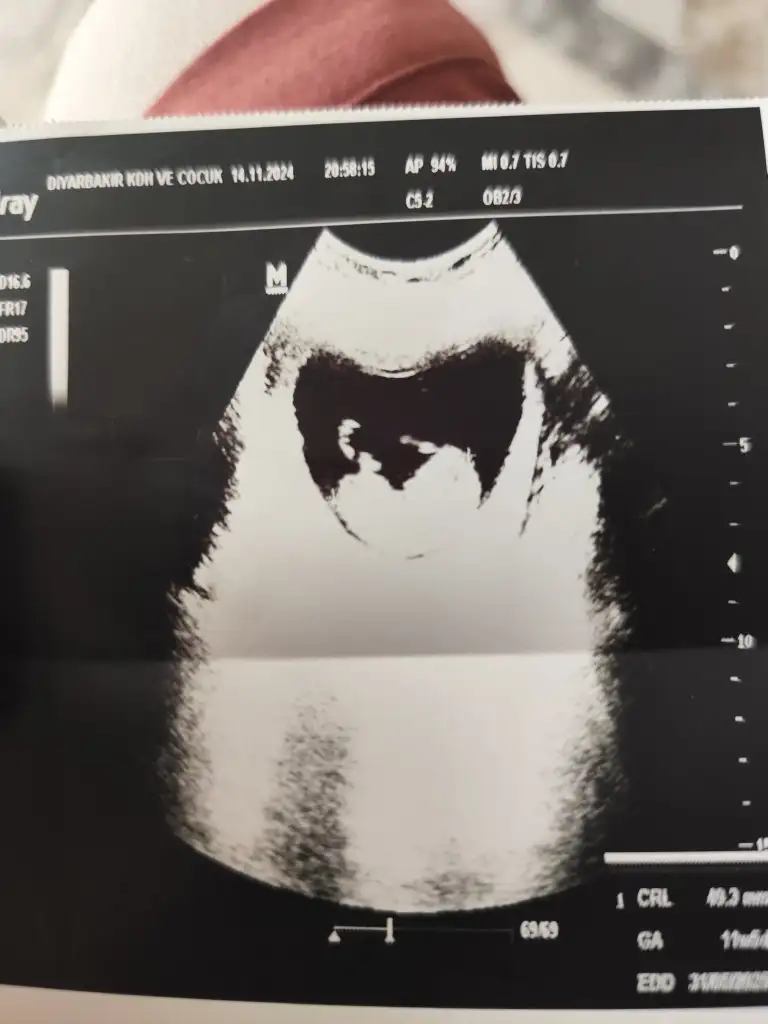

Merhaba benim bebeğimi de tahmin edermisiniz

Sata göre 11 haftalık

• 1000023488.webp

1000023488.webp

21,3 KB · Görüntüleme: 94

Lütfen benim bebeğimi de tahmin edermisiniz doktor beş aya kadar söylemiyor

21,3 KB · Görüntüleme: 75